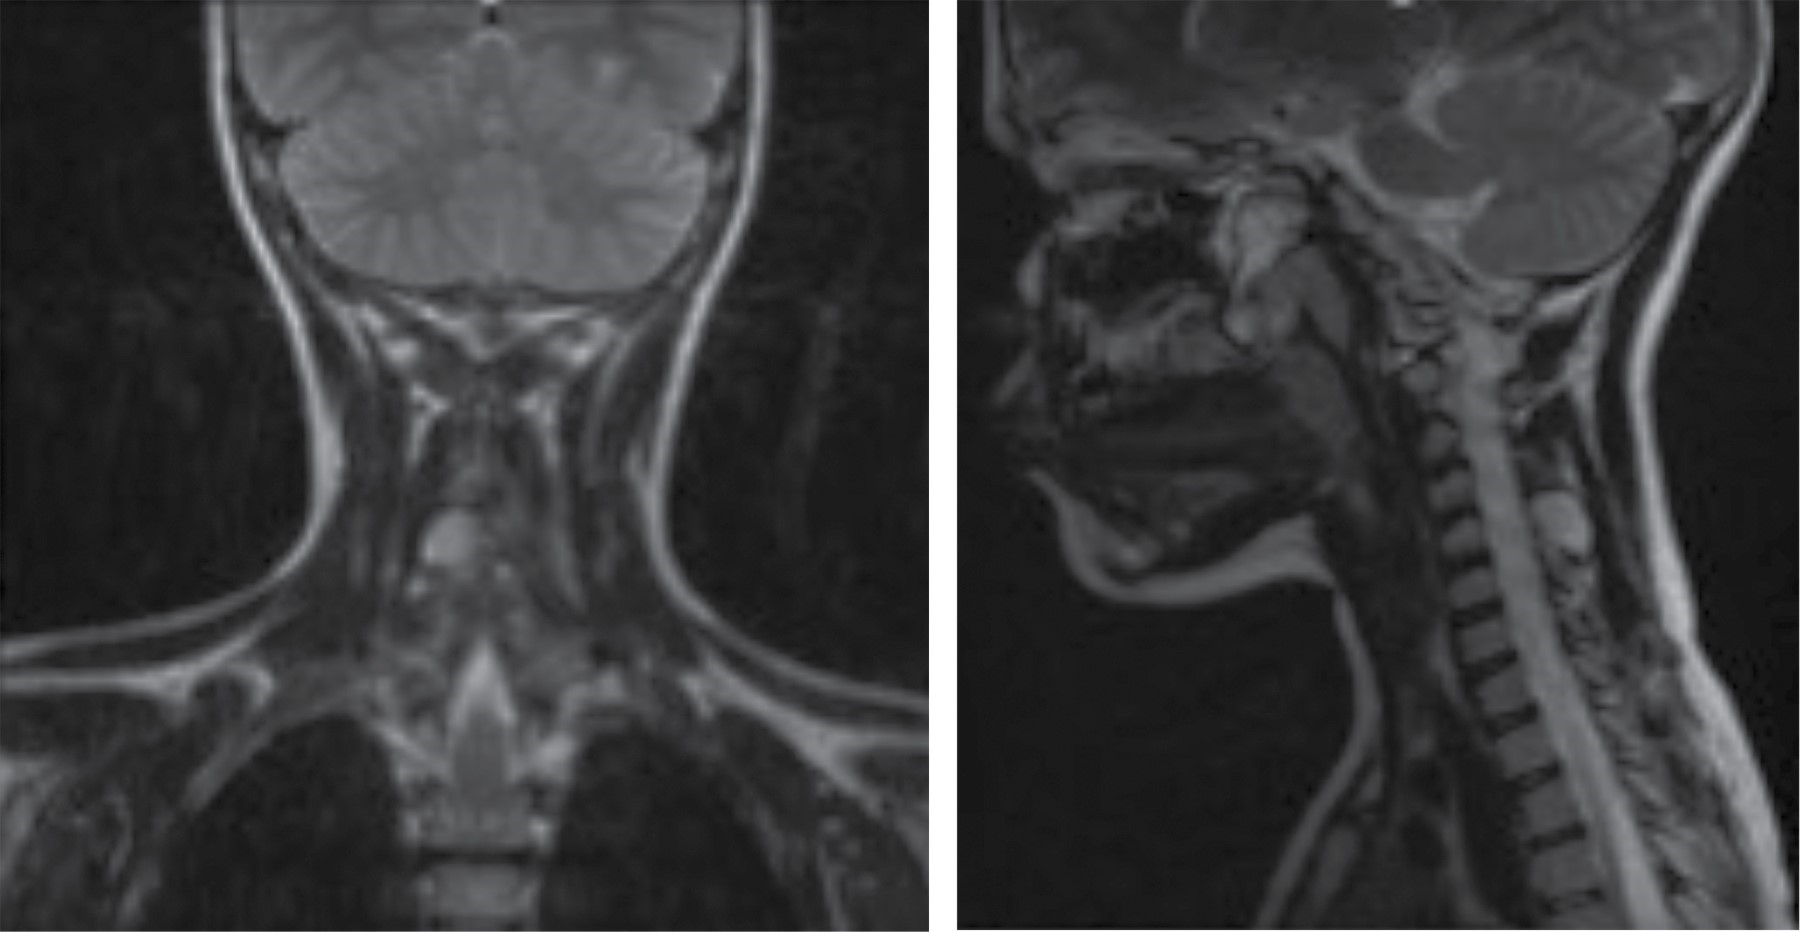

Se solicitan estudios de analítica sanguínea, en los que se encuentra fosfatasa alcalina de 312 unidades/litro que se considera normal por actividad ósea fisiológica; ultrasonografía con reporte de lesión sólida de componente óseo paracervical derecho, probable osteocondroma; tomografía axial computarizada simple donde se aprecia imagen hiperdensa en lámina derecha de quinto cuerpo vertebral, única, de aproximadamente 15 × 20 mm (Figura 3); resonancia magnética nuclear simple que reporta imagen hiperintensa que rebasa bordes, de aproximadamente 15 × 20 mm, en lámina derecha de quinto cuerpo vertebral (Figura 4) y gammagrafía ósea con MDP que indica actividad osteoblástica con discreto aumento en quinto cuerpo vertebral cervical principalmente lado derecho, no se observan zonas de infiltración ósea.

Figura 4